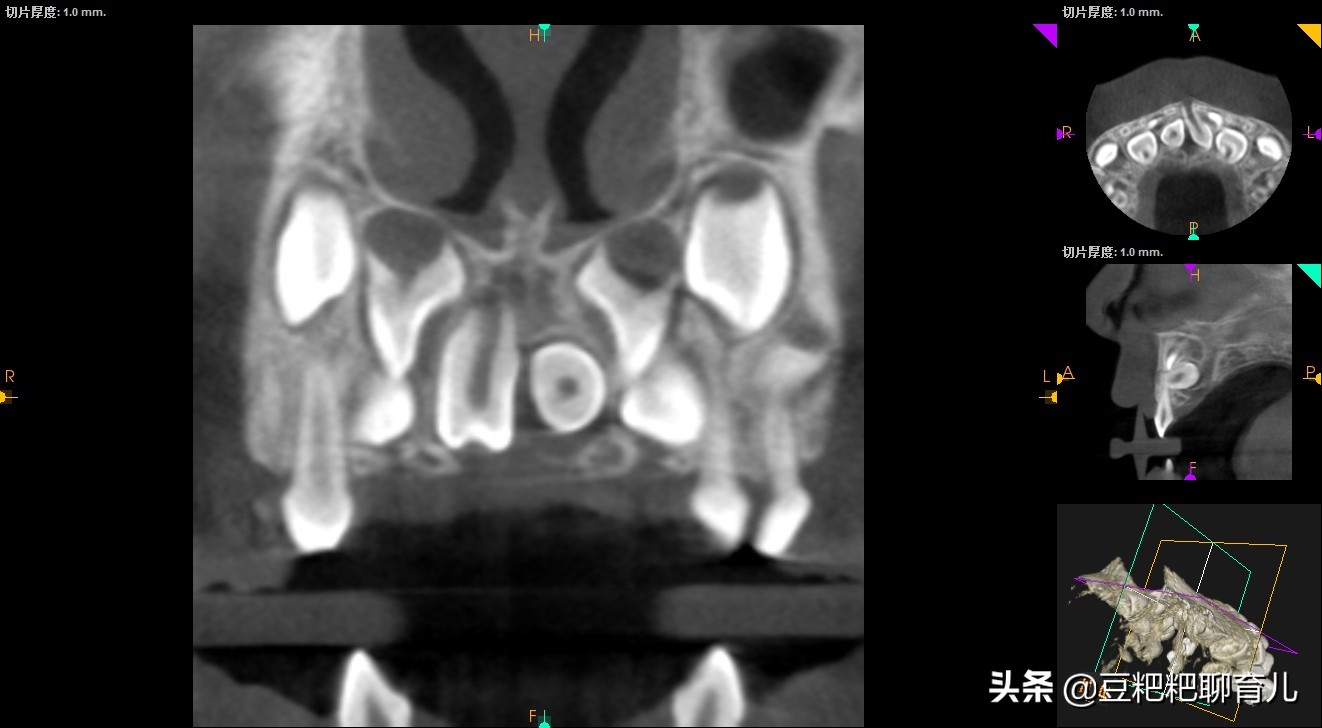

我儿子的就是"埋伏性正中多生牙",就是从表面看不见生长在牙龈里面,需要照X光才能发现。而且一颗是正常生长的,一颗是横着长的。